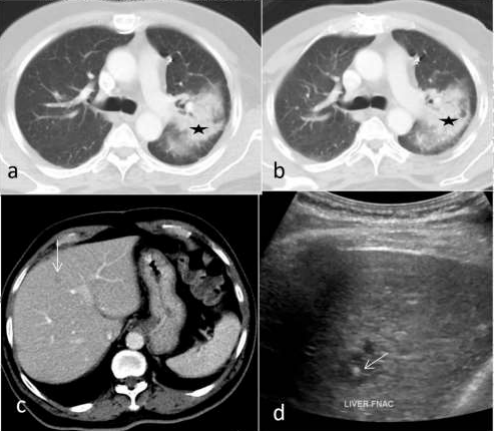

Prior to FNAC/biopsy, liver lesion is evaluated with ultrasound, approach decided and point of entry is marked on skin. FNAC / biopsy can be done using either intercostal, subcostal or transabdominal / sub- xiphoid approach depending upon the location of the liver lesion. (Fig. 1) Then entry site and surrounding area is cleaned with alcohol / betadine. Transducer and wire is covered with sterile probe cover with jelly inside over the transducer, which is important to avoid soiling of the probe and to maintain proper aseptic technique. Local anesthesia with 2% lignocaine is given at the site of entry involving skin and underlying soft tissue along the proposed needle trajectory. Then under ultrasound guidance, a FNAC / biopsy needle is inserted into the lesion avoiding the vessels. Keep the tract of the needle tangential to the ultrasound beam, with this entire tract of the needle can be visualized and, vessels can be avoided using color doppler technique. It is always preferred to put the needle parallel to the vessels and not perpendicular to it, to avoid transection of vessels while taking cores with a gun. (Fig. 2, 3 and 4) We prefer to do the procedures during normal breathing and the needle can be advanced in whichever phase of respiration the lesion is more conspicuous. However, for smaller lesions, those located beneath the rib and deeply seated lesion in segment VII/VIII, breathhold (either during inspiration / expiration) is required. (Fig. 5) While doing FNAC, move the needle to & fro and let the sample collect in the needle with the capillary action and check for the same by looking at the needle hub. If the sample does not collect in the needle, then gentle suction with a syringe is given. Care should be taken not to give excessive negative pressure in the syringe to prevent hemorrhagic aspirate. Generally it requires 2-3 passes for FNAC. Slides are prepared from the aspirate and transferred to the coplin jar containing 95% ethyl alcohol solution. It is better to perform the procedure under the presence of cytologists who can check for the adequacy of the sample obtained and avoiding inconclusive FNAC and repeat procedures. For biopsy, after confirming the position of the needle in the lesion (preferably at the periphery in larger lesion), semiautomatic biopsy gun is inserted and cores are taken. At least 4 cores in 4 different directions of the curing edge are taken and transferred to the container containing formalin.

Figure 01: (A) Intercostal Approach – USG guided FNAC of segment IV liver lesion (red arrow). White arrow denoted ribs and yellow arrow FNAC needle. (B) Transabdominal / Sub-xiphoid Approach – USG guided biopsy of segment III liver lesion (red lesion). White arrow denoted anterior abdominal wall and yellow arrow biopsy needle.